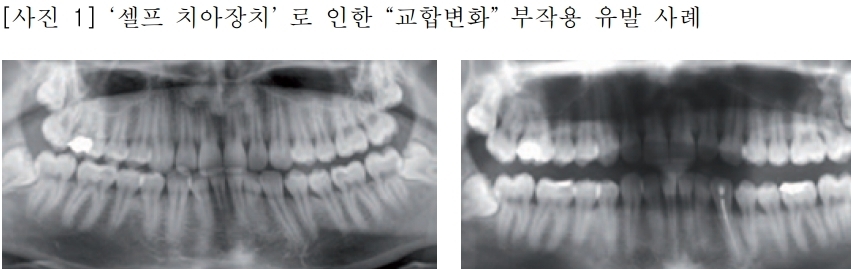

일부 온라인 쇼핑몰에서 치과의사의 진단 없이 이갈이, 코골이 방지 또는 치아교정 효과가 있는 것처럼 홍보하며 마우스피스를 판매하고 있다. 그러나 이러한 ‘셀프 치아장치’는 효과를 담보할 수 없을 뿐 아니라, 치아나 잇몸 손상, 부정교합, 턱관절 장애, 파손으로 인한 기도흡입 등 심각한 부작용을 유발하는 것으로 확인됐다.

실제로 건강한 생활을 위해 ‘셀프 치아장치’를 사용했다가 ▲치아 및 잇몸 손상 ▲부정교합 ▲턱관절 장애를 겪는 사례가 빈번하게 발생하고 있다. 한 소비자는 ‘셀프 이갈이 방지 장치’를 2주간 사용한 후 "양치와 음식 섭취가 고통스럽다"는 후기를 남겼으며, 구강 내 점막궤양이 유발된 것으로 보인다.